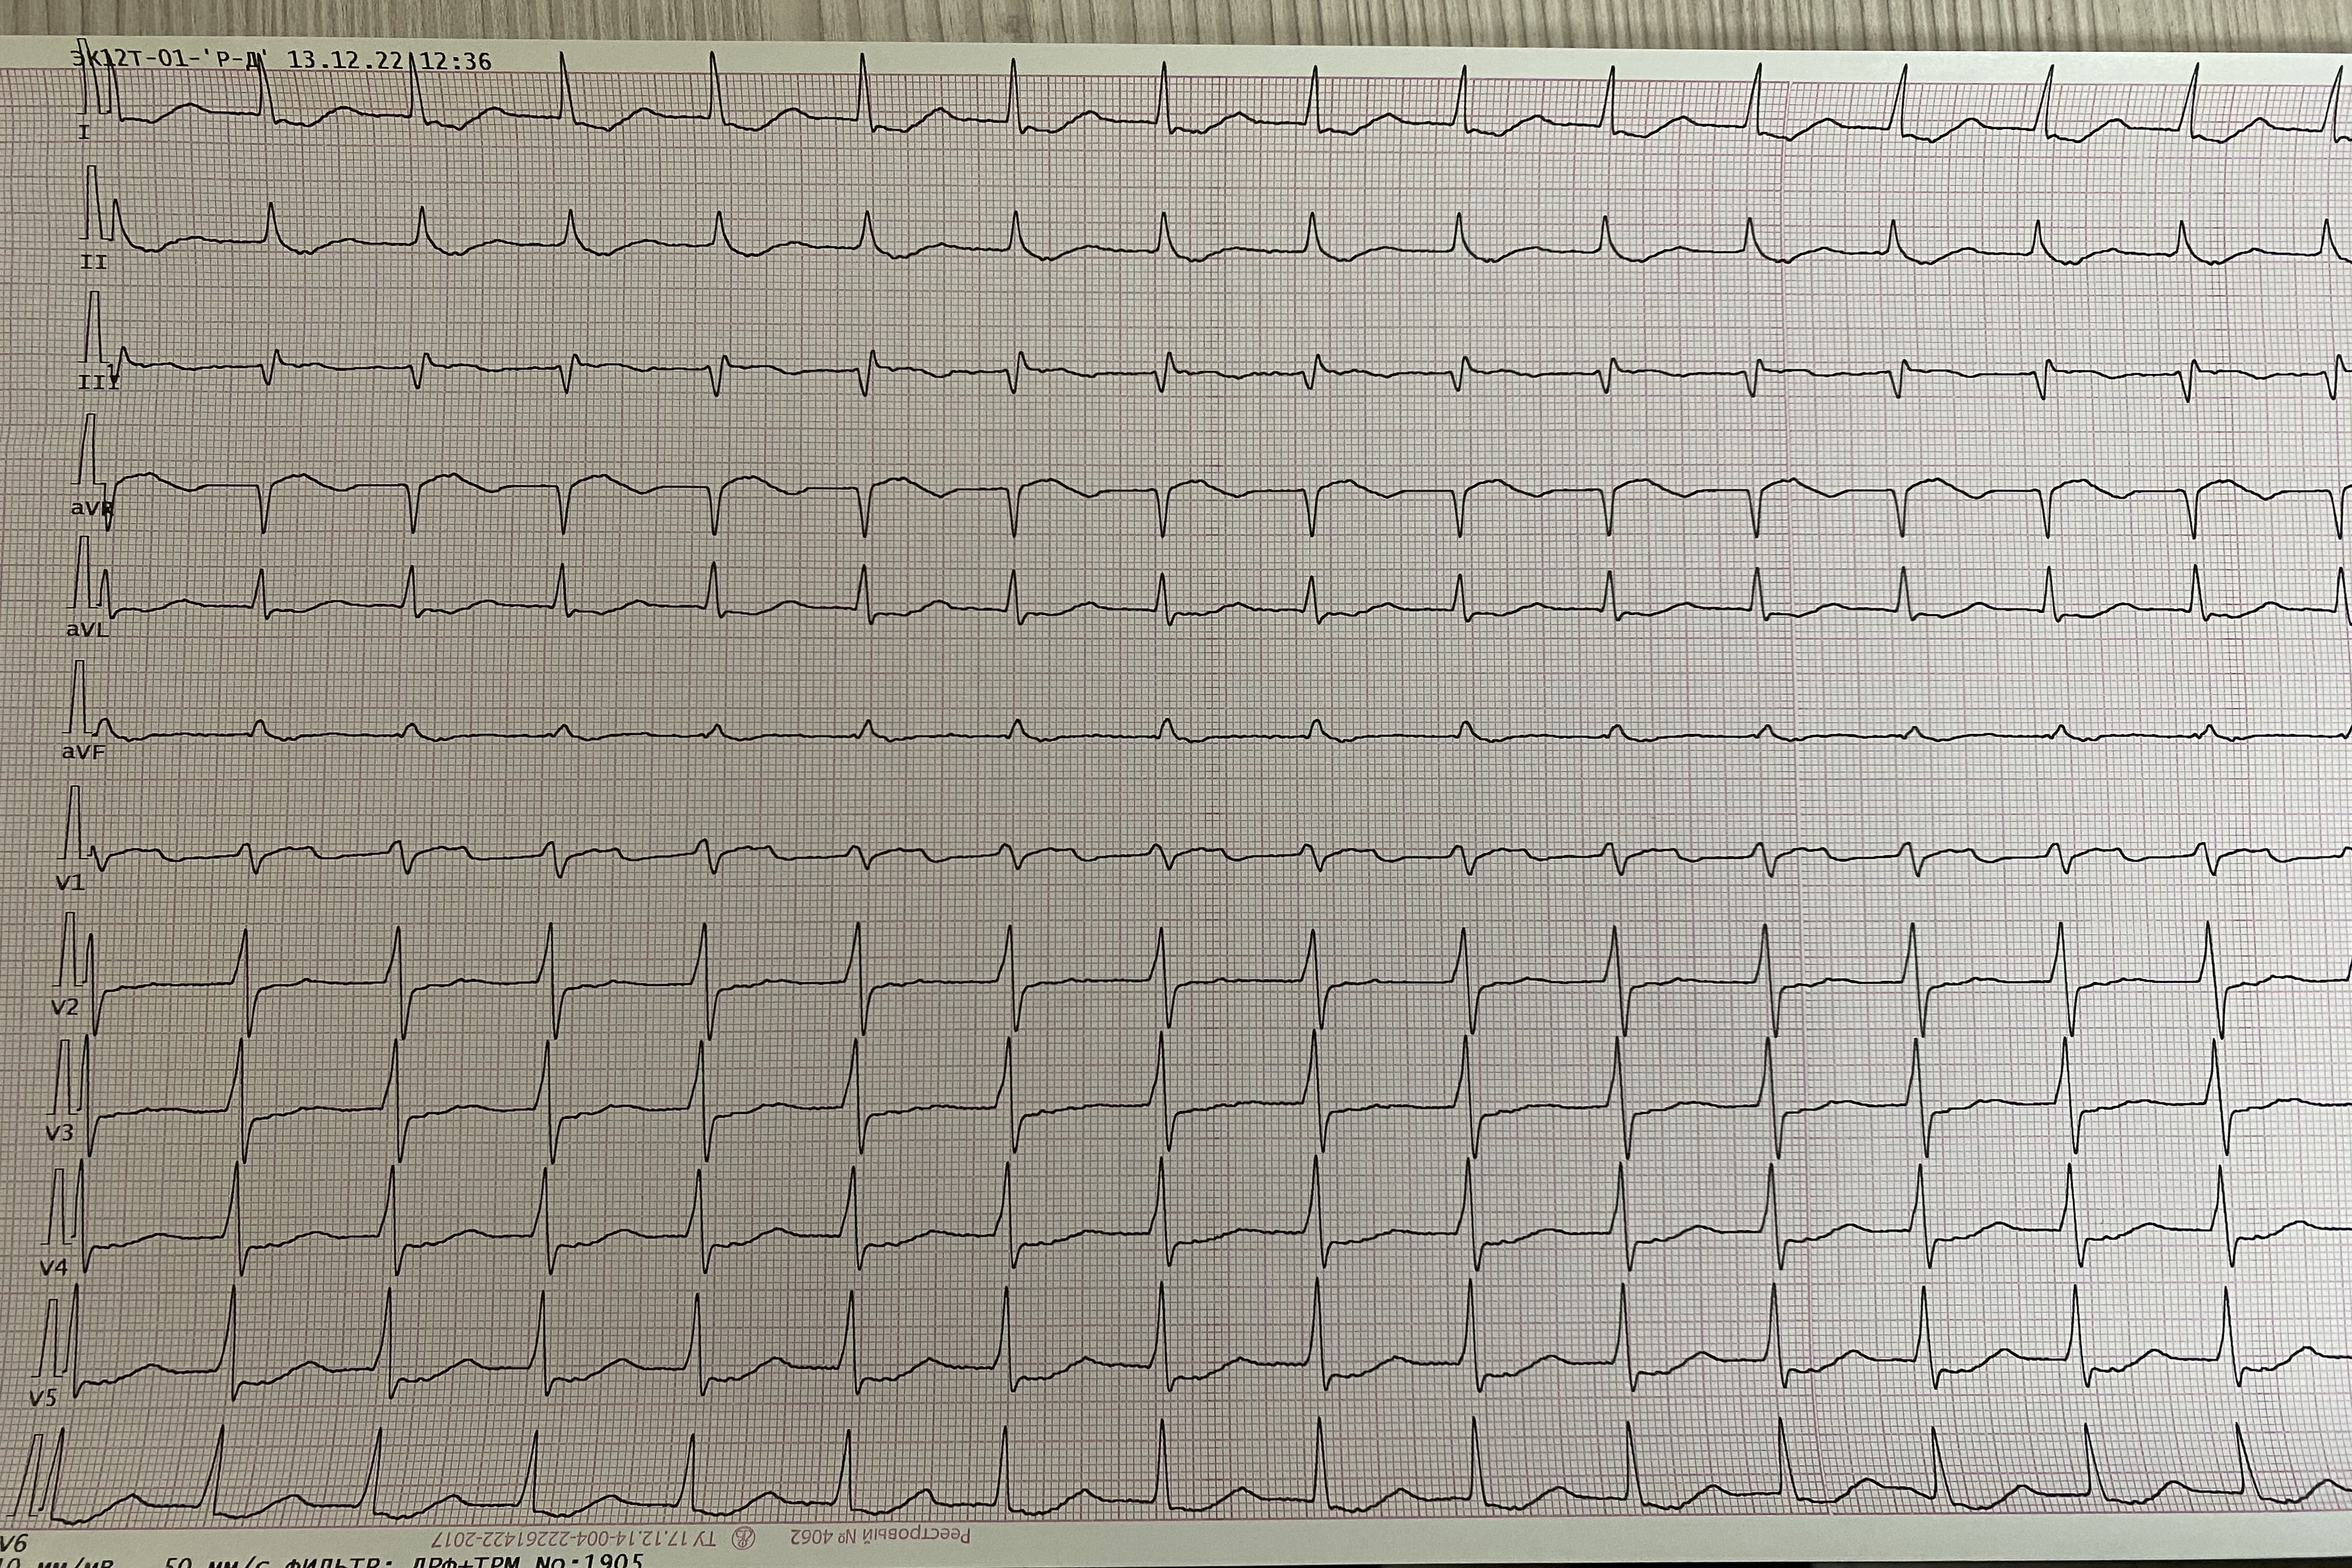

Обсуждалось здесь https://vk.com/club84409679?w=wall-84409679_13416%2Fall

IMG_1405.jpg

IMG_1405.jpg [ 4.29 MiB | Просмотров: 6351 ]